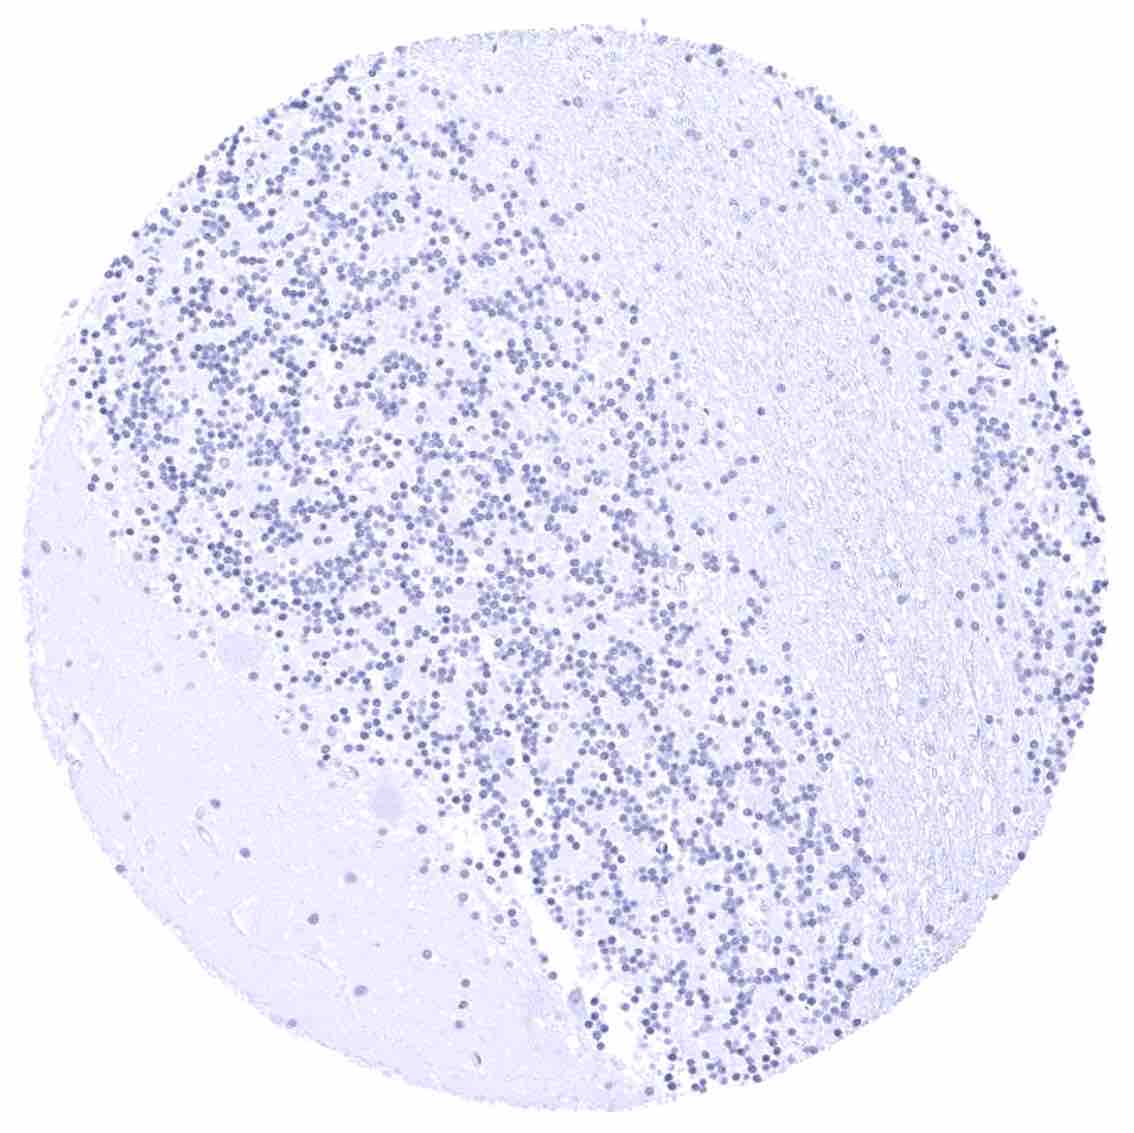

Lymph node – Strong bcl-2 positivity of a large fraction of lymphocytic cells in the interfollicular area and around germinal centres while almost all cells in germinal centres are bcl-2 negative.